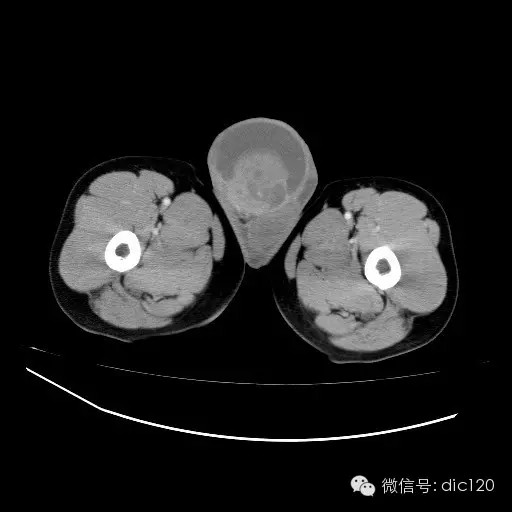

【影像表现】

青年男性,右侧睾丸肿大,边界清晰,增强后睾丸不均匀中度强化,内可见多灶囊变坏死区,动脉期肿块内有细小动脉血管显示,延迟期可见分隔样强化,鞘膜囊可见积液。

定位定性:右侧睾丸恶性肿瘤。

【影像诊断】

右侧睾丸精原细胞瘤,右侧睾丸鞘膜积液。